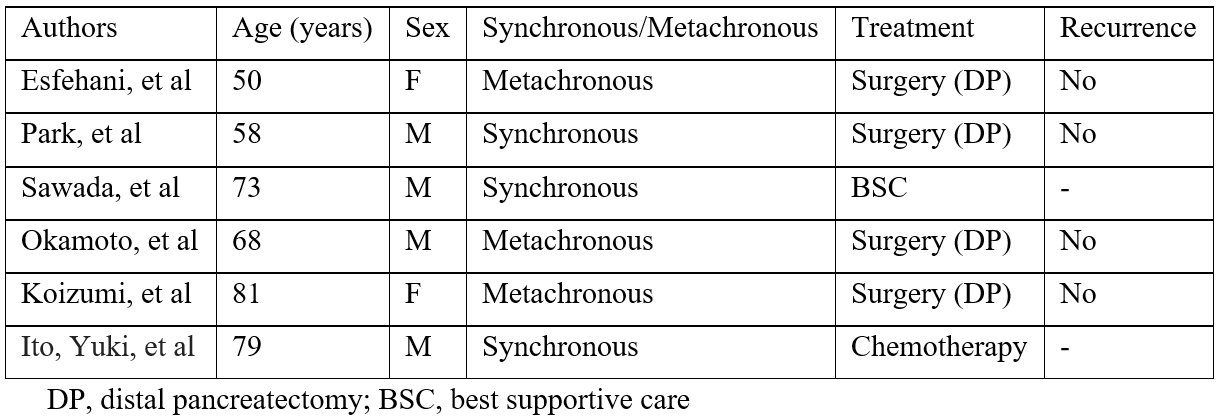

Squamous cell carcinoma with pancreatic metastasis is rare. It occurs in 0.12% of all esophageal squamous cell carcinoma [13]. So far only six cases have been reported of esophageal squamous cell carcinoma with pancreatic metastasis (Table 1) [14-18]. Three cases were diagnosed synchronously, and three metachronously. Among these 6 cases three with metachronous pancreatic metastasis and one with synchronous were treated surgically i.e distal pancreatectomy and one patient was offered chemotherapy and one was treated with best supportive care. As squamous cell carcinoma can arise not only from the esophagus but also from the pancreas or bile duct, the esophageal origin of the tumor can only be confirmed with special stains which are unique to oesophageal origin such as p40+, which was positive in our case confirming metastases from oesopahgeal origin.

Table 1: Reported cases of pancreatic metastasis from esophageal squamous cell carcinoma.

The interval between the diagnosis of the primary oesophageal cancer and the pancreatic metastasis ranged from 0 to 132 months [18] with our case having the interval of 50 months.